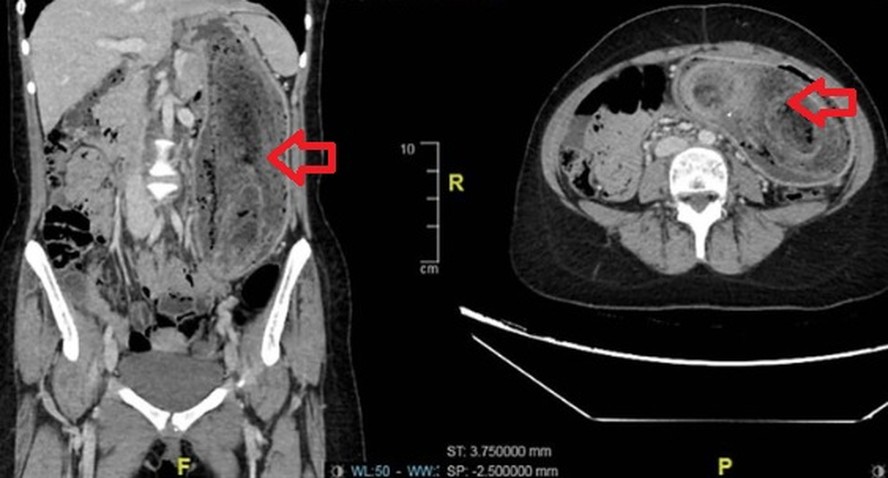

Massa de cabelos foi retirada de estômago de adolescente — Foto: Divulgação/Journal of Surgical Case ReportsOs médicos notaram que o abdômen estava inchado e dolorido, com uma massa firme palpável. Exames de imagem confirmaram o diagnóstico: um enorme aglomerado de cabelos ocupava todo o estômago e se estendia até o duodeno, o que caracteriza a chamada "síndrome de Rapunzel".

Exames mostraram enorme aglomerado de cabelos ocupava todo o estômago e se estendia até o duodeno — Foto: ReproduçãoA paciente se recuperou bem, recebeu alta quatro dias depois e foi encaminhada para avaliação psiquiátrica e terapia comportamental para evitar que a situação se repita.